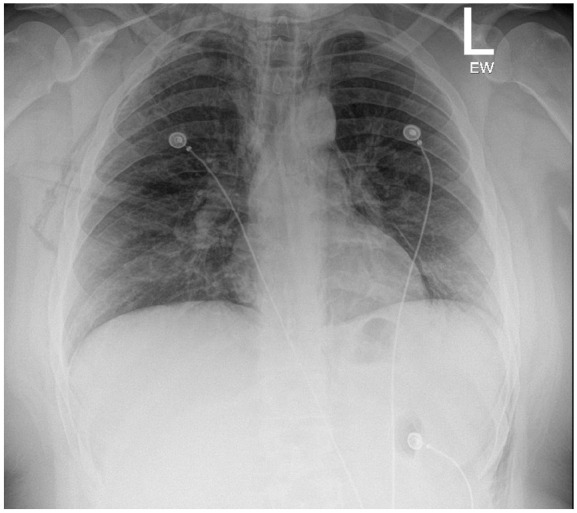

Spontaneous pneumomediastinum (SPM) is a rare, self-limiting condition that can be complicated by pneumothorax, pneumopericardium, and subcutaneous emphysema. This case describes a 25-year-old man with a chronic marijuana use history who developed SPM after a recent respiratory infection. Imaging showed significant pneumomediastinum, pneumopericardium, and small pneumothoraces bilaterally. Despite these findings, he remained stable and was treated conservatively with oxygen supplementation, analgesics, and close monitoring. By day 6, his condition had nearly resolved, and he was safely discharged. This case emphasizes the importance of considering SPM in young patients with acute respiratory distress and reinforces the value of computed tomography scans in promptly diagnosing and managing the condition without invasive interventions.